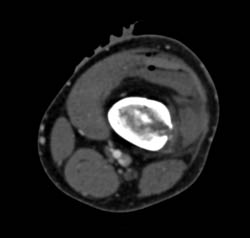

Dislocated Hip With Fracture